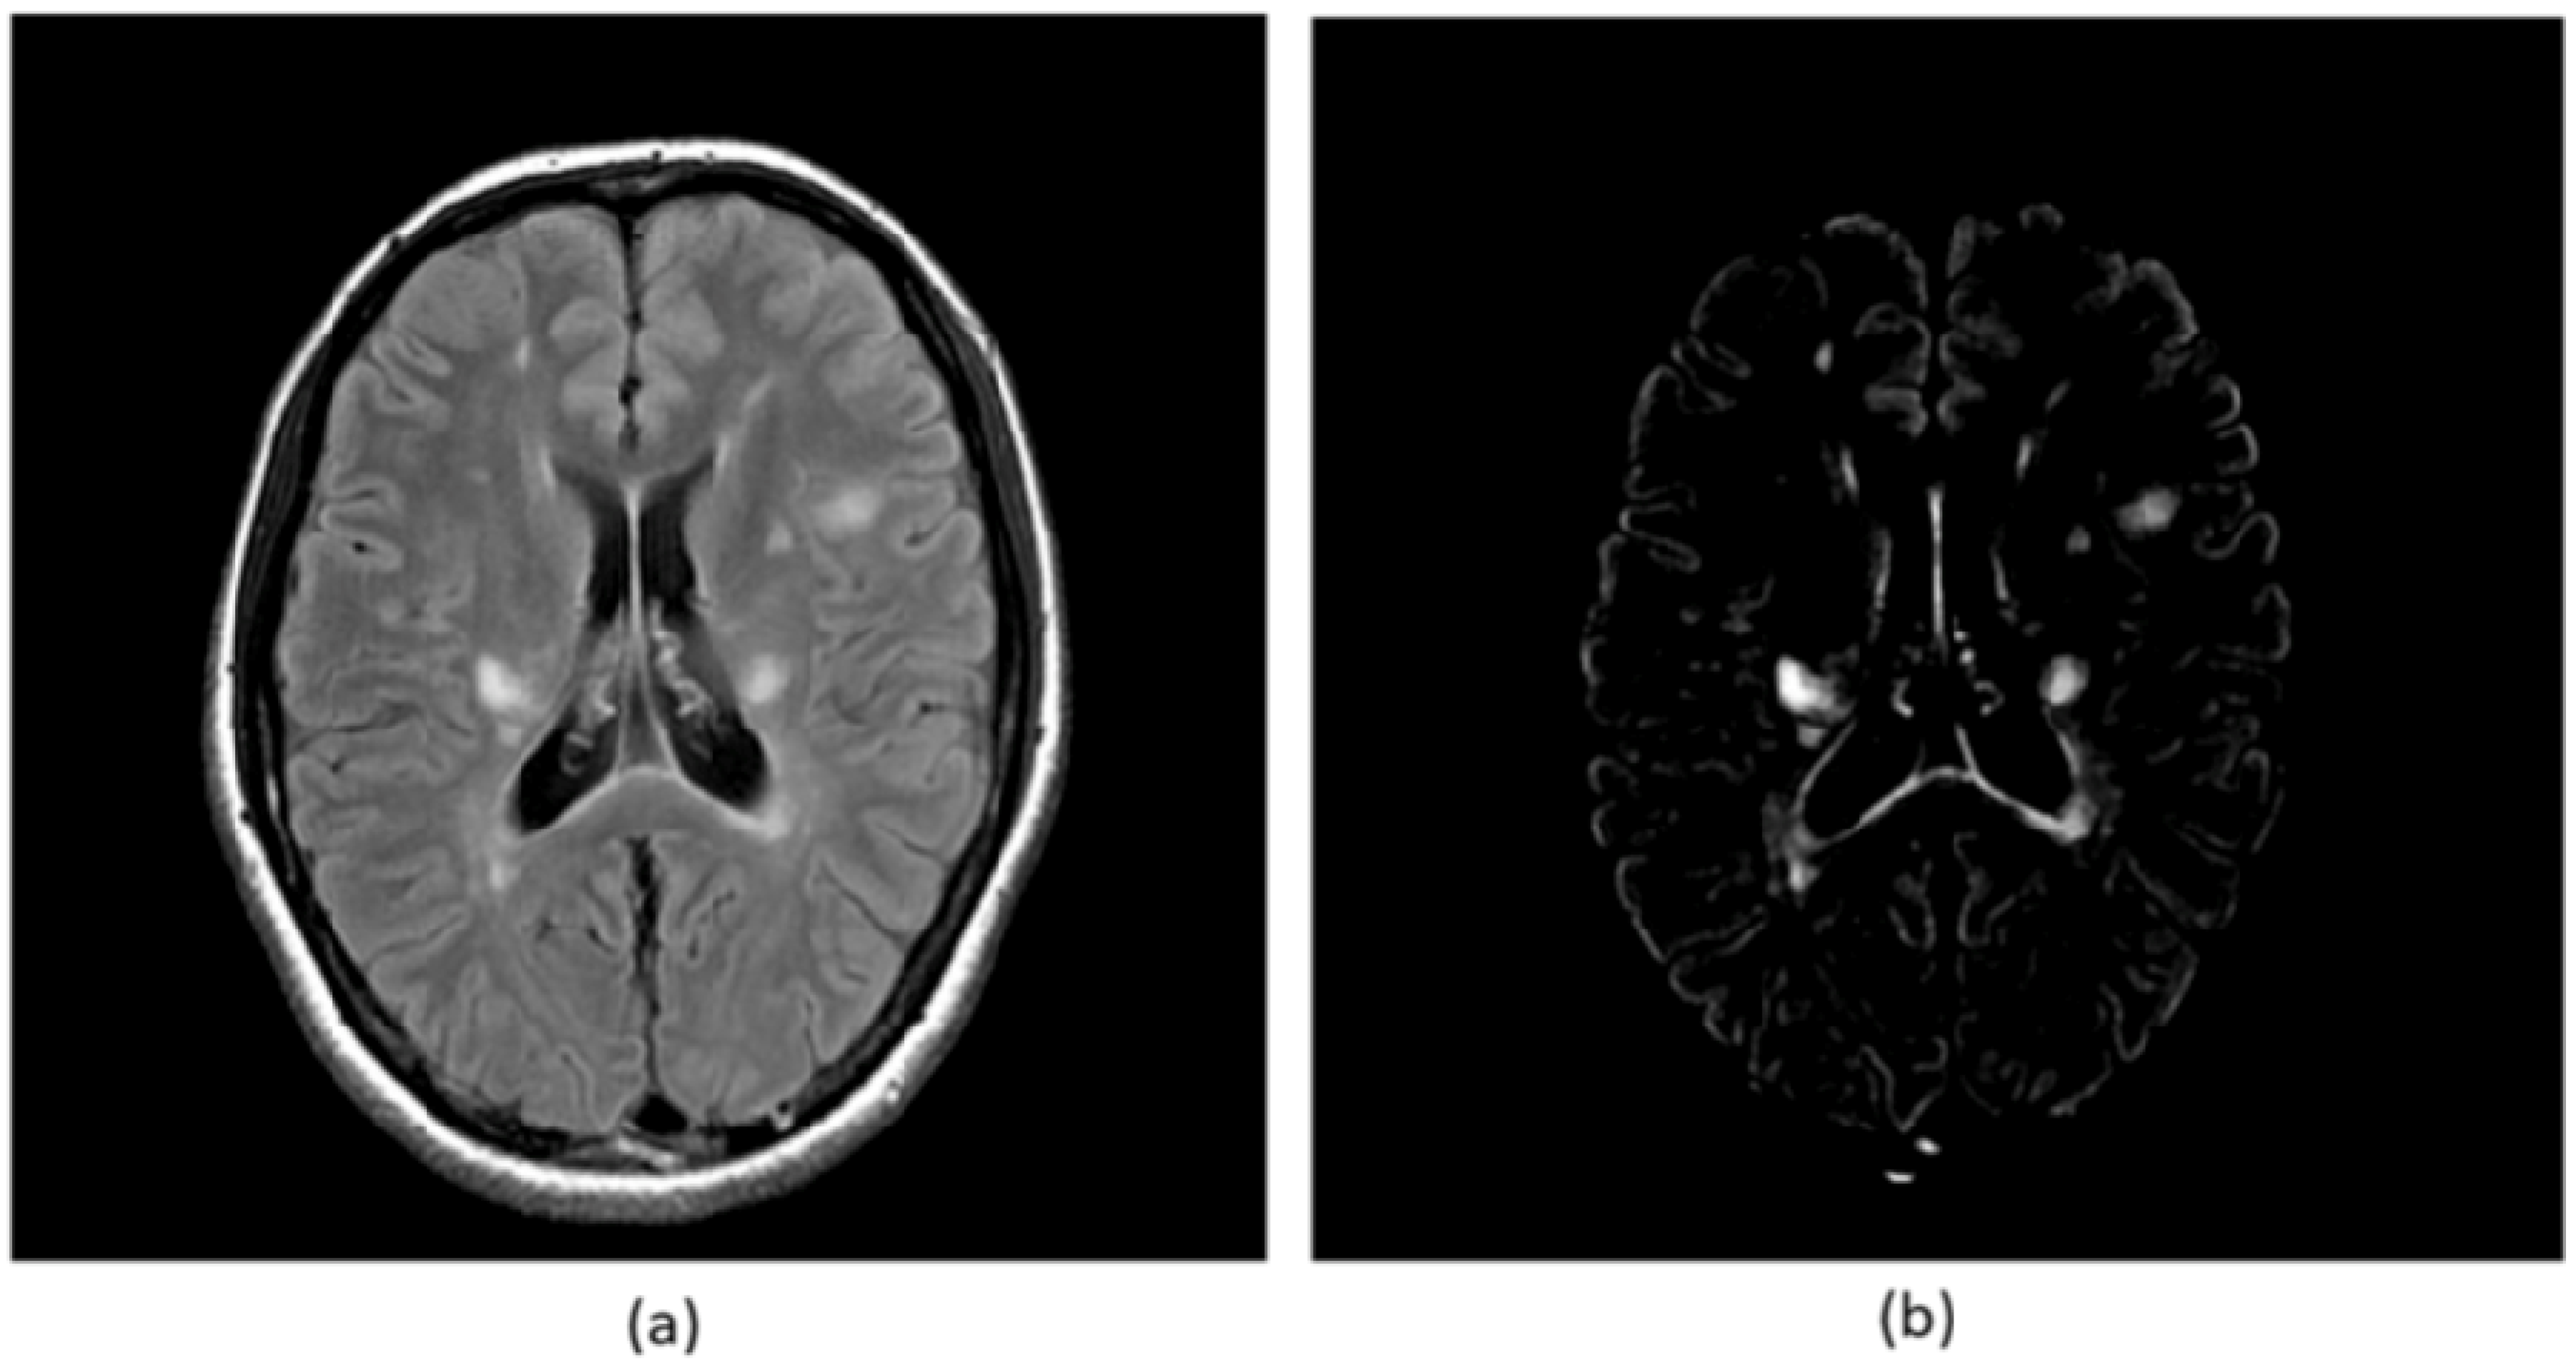

Figure 5.

Illustrations of (a) an original FLAIR image, and (b) its corresponding subtraction image between the FLAIR image and a background image approximated by the first order polynomial in a brain region [30,31].